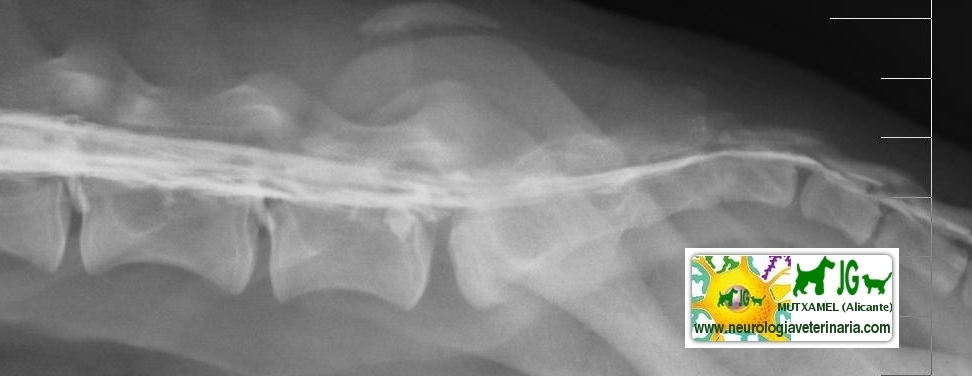

![]() por Juan M. Griñán. Veterinario ![]() comparativa entre una mielografía (mostrando la aguja) y una resonancia magnética, secuencia SE T1w (mostrando donde está el saco dural, sitio para la inyección del contraste). Nótese la extravasación del contraste yodado en la mielografía. | |||||||||